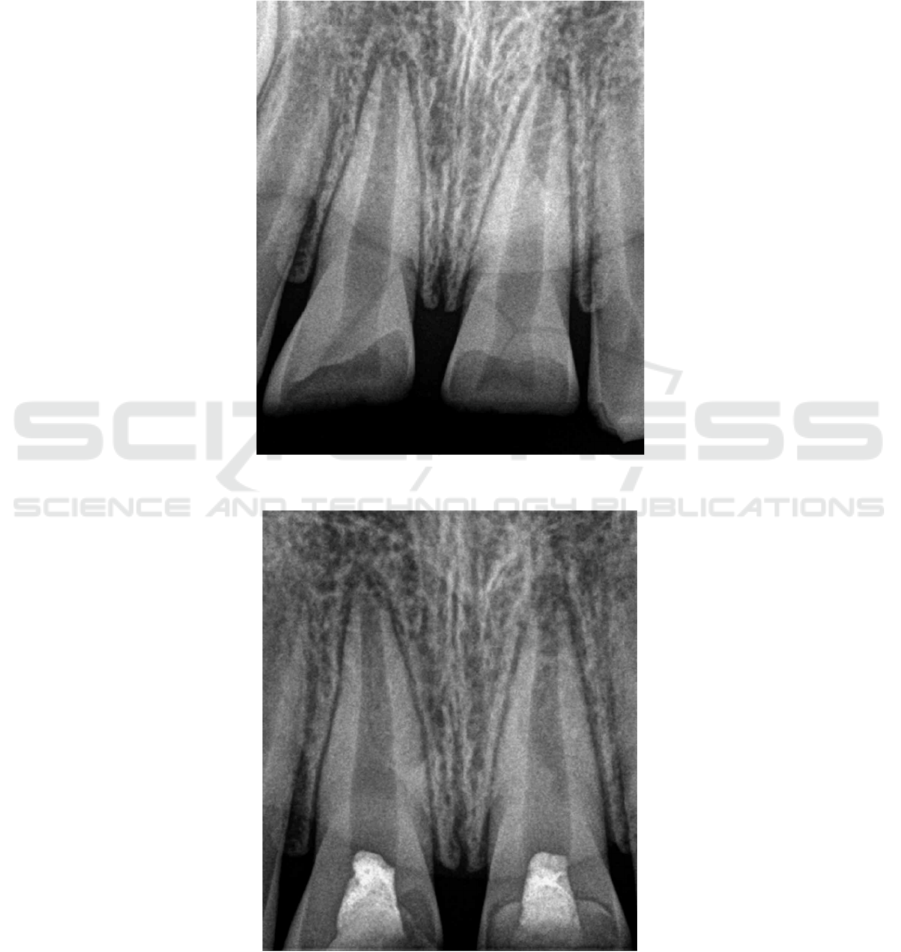

Rradiographic examinationas showed that roots of

tooth 11 and 21 were under developed with open apex,

as is shown in Fig.1. The fractured teeth are treated

The re-examination results showed that tooth 11

and 21 had no obvious discomfort. Radiographic

examination at 6 month showed that dentin bridge

under iRoot BP Plus existed without any sign of

pathology, as is shown in Fig.3a. In addition, the

reviewed radiographic examination at 12 month

showed that the roots walls thickened and the apical

foramen tended to converge, as is shown in Fig. 3b.

Figure 1: The preoperative periapical radiograph of tooth 11 and 21 with open apex.

(a)The reviewed radiograph at 6 month.

(b) The reviewed radiograph at 12 month.

Figure 3: The reviewed periapical radiograph of the case.